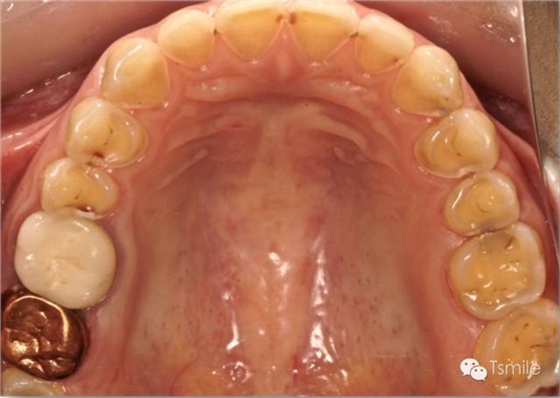

圖5: 胃食管返流病導(dǎo)致的牙列重度磨耗 牙列重度磨耗的病因的鑒別診斷 牙列重度磨耗病因復(fù)雜,磨耗類(lèi)型多樣,很多病例往往多病因混合或交替致病,造成對(duì)病因的鑒別診斷困難。臨床上可以結(jié)合病史和口腔檢查兩方面進(jìn)行病因的鑒別診斷。 病史是牙列重度磨耗病因診斷的重要環(huán)節(jié)。如果通過(guò)病史詢(xún)問(wèn)確定患者有夜磨牙病史,這就提示我們物理因素可能是牙列重度磨耗的主要病因。如果通過(guò)病史詢(xún)問(wèn)確定患者有胃食管返流病,這就提示我們化學(xué)因素(酸蝕癥)可能是牙列重度磨耗的主要病因。因此,病史可以為牙列重度磨耗的病因診斷提供非常重要的信息和依據(jù)。 除了病史詢(xún)問(wèn),對(duì)牙列重度磨耗病因的鑒別診斷還要結(jié)合口腔檢查,即對(duì)牙齒表面磨耗特征的檢查。區(qū)分牙列重度磨耗是物理性的磨耗(attrition)還是化學(xué)性的酸蝕癥(erosion),主要可以根據(jù)牙齒磨耗發(fā)生的部位(location)、磨耗面外觀特征(appearance)、上下頜相對(duì)牙齒的磨耗量對(duì)比(amount)、上下頜相對(duì)牙齒的磨耗面是否有咬合接觸(contact)等這四個(gè)主要因素來(lái)進(jìn)行鑒別診斷, Frank Spear 稱(chēng)之為L(zhǎng)AAC原則。 磨耗發(fā)生的部位(location)物理性的磨耗由于是上下頜牙列相對(duì)的牙齒之間的機(jī)械摩擦而導(dǎo)致,因此物理性的磨耗主要發(fā)生在牙齒的咬合面。而酸蝕癥導(dǎo)致的牙列重度磨耗不一定在牙齒的咬合面,可以發(fā)生于牙齒的唇頰面或者舌顎面。

圖2: 長(zhǎng)期飲用碳酸飲料導(dǎo)致的酸蝕癥 2.磨耗面外觀特征(appearance) 物理性的磨耗形成的磨耗面邊緣尖銳、表面光滑閃亮。而酸蝕癥導(dǎo)致的磨耗面邊緣圓鈍,多呈杯狀凹陷。 3.上下頜相對(duì)牙齒的磨耗量對(duì)比(amount) 物理性的磨耗上下頜相對(duì)牙齒牙面的磨耗量基本一致。而酸蝕癥導(dǎo)致的牙列重度磨耗上下頜相對(duì)牙齒牙面的磨耗量可以完全不同,甚至一側(cè)有嚴(yán)重的磨耗而對(duì)側(cè)完全沒(méi)有磨耗。 4. 上下頜相對(duì)牙齒的磨耗面是否有咬合接觸(contact) 物理性的磨耗所導(dǎo)致的牙列重度磨耗,其上下頜相對(duì)牙齒的磨耗面之間一定有咬合接觸。而化學(xué)性酸蝕癥所導(dǎo)致的牙列重度磨耗,其上下頜相對(duì)牙齒的磨耗面之間可能完全沒(méi)有咬合接觸。